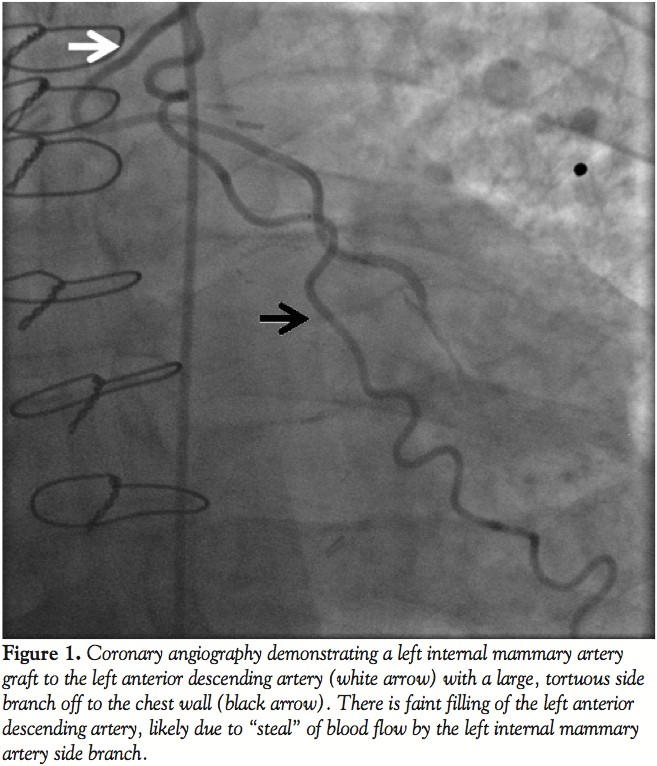

Left radial access was obtained with a 6 Fr sheath. The LIMA was wired with an Ironman wire (Abbott Vascular; Figure 2) and a Proxis catheter (St. Jude Medical) was inserted into the LIMA side branch (Figure 3). We attempted to deliver a 3 mm Amplatzer vascular plug (AGA Medical) through the Proxis catheter in the LIMA side branch, however significant resistance was encountered during delivery attempts. The device was partially deployed but in suboptimal location due to movement of the catheter during delivery. The vascular plug was recaptured and removed. LIMA angiography demonstrated side-branch occlusion. The LIMA side branch remained occluded after 15 minutes of observation. The patient had an uneventful recovery and has had no recurrent angina during 3 months of follow-up.